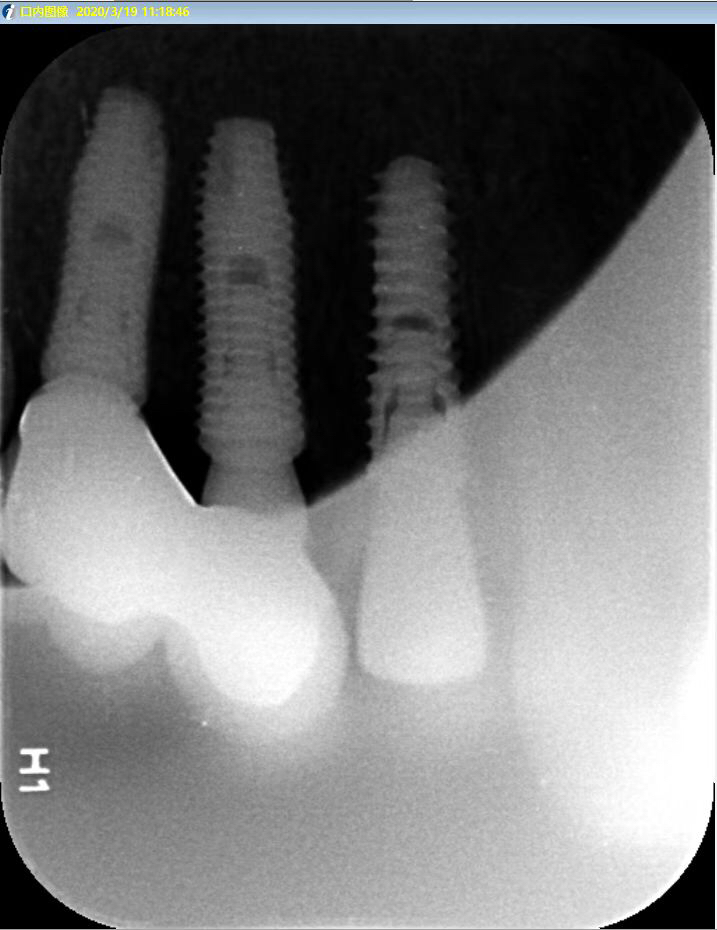

患者女,右上4号牙根管治疗后桩核冠修复,因进食硬物导致桩核冠脱落,未及时处理,导致残根无法修复,从CT上看,牙槽骨高度尚可,所以选择了即拔即种的治疗方案,且术中植骨盖膜、上愈合基台,为患者节省了就诊次数,提前了戴牙时间。